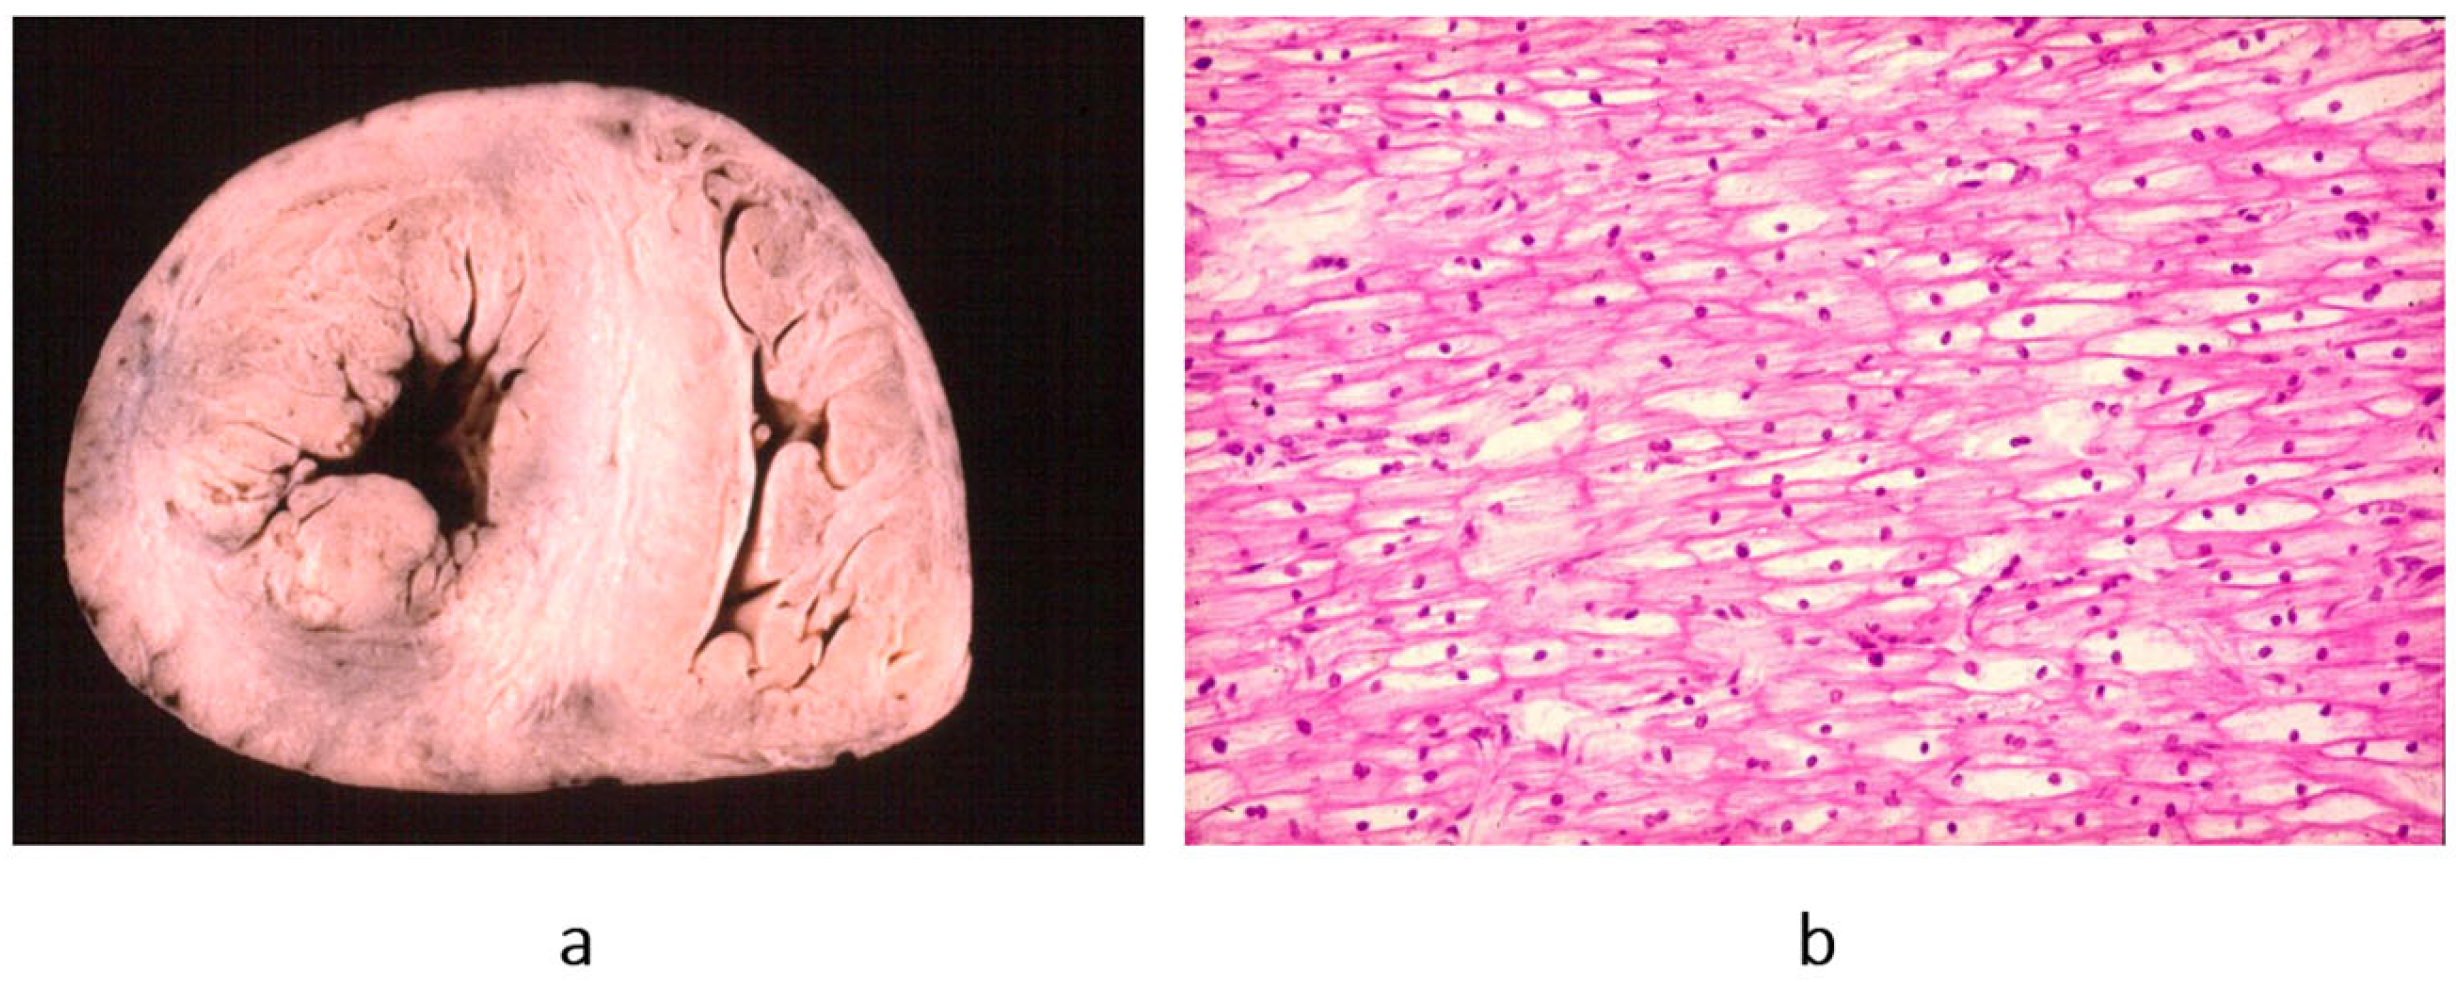

Concerning dilated cardiomyopathy, ventricular dilatation (Figure 2a and Figure 4a) can be due to poor contractility caused by myocytolysis (Figure 4b) or previous viral myocarditis with scarring from necrosis (Figure 5).

Figure 4. Example of a heart with dilated cardiomyopathy, gross view (a), and myocytolysis of cardiomyocytes on histology (b), haematoxylin–eosin stain. From [3] with permission.